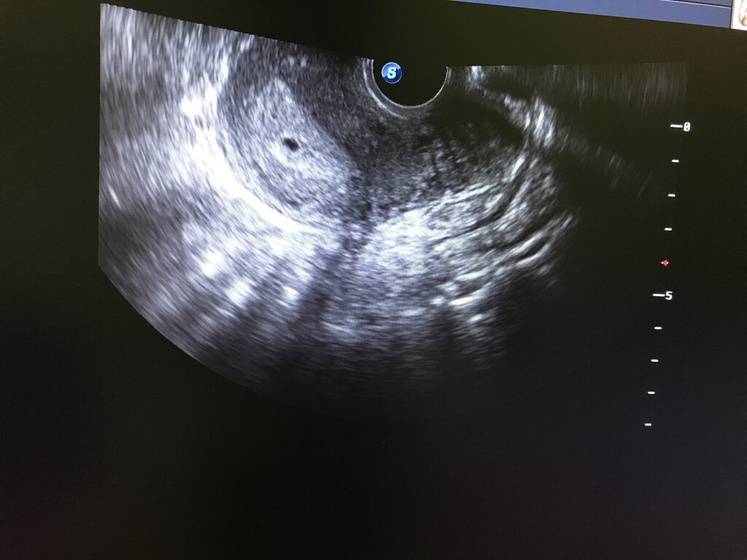

Смотрела и читала в инете, что вот с чёрной точечки потом внутри может один быть эмбрион, а может и два… они на раннем этапе будут как шарики внутри, я тут уже как не увеличивала, даже два увидела ???

Вот типа такого) у меня пока только чёрное видно, а потом уже видны эмбрионы… или эмбрион ?